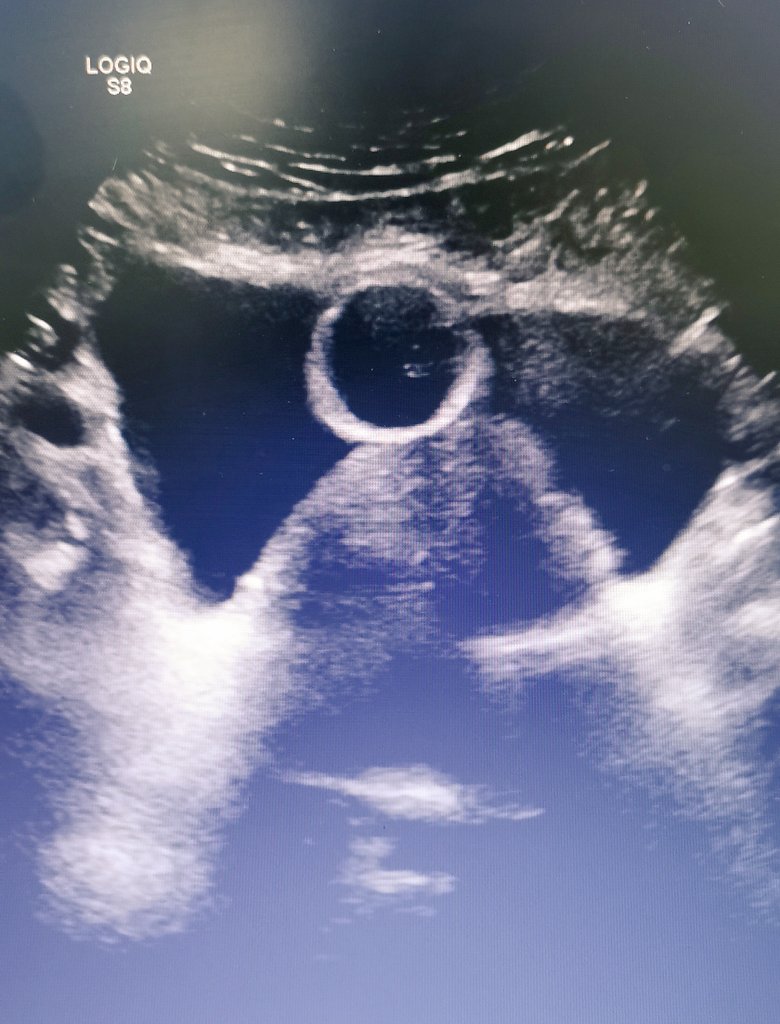

73 yrs old, prostate with 263 grams. In using of cistostomy for 6 months. Open adenomectomy is still an option for poor countries where AEEP is not an option.

#UroSoMe#UroSoMeBrasil pic.twitter.com/SUelqQARoi – mjesto: Hospital de Clínicas da UFPR